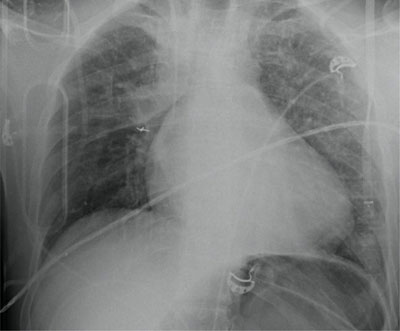

A 41-year-old man was admitted to the emergency department (ED) after a high-velocity car accident. He was ejected out of his vehicle. He had a severe bleeding head wound, symmetric breathing, and normal abdominal findings. Blood pressure and saturation were normal. On arrival to the hospital the patient had worsening bradypnea and bilateral rhonchi. A chest X-ray (Figure 1) shows multiple left sided rib fractures without pneumothorax and blurry consolidations in both lungs, probably lung contusions.

Figure 1

Multiple left sided rib fractures without pneumothorax and blurry consolidations in both lungs, probably lung contusions.